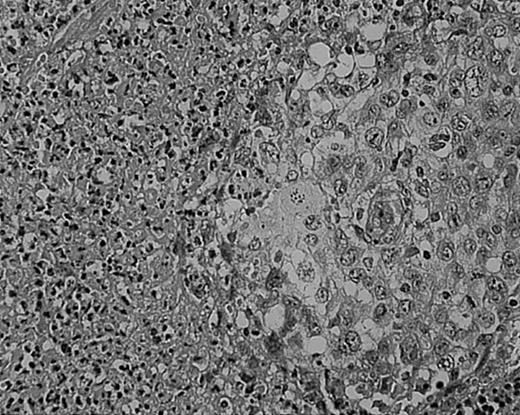

As we have previously reported, tissue eosinophilia is the strongest prognostic indicator in NS.19 Eosinophilia was not included in the BNLI criteria. We therefore propose a new grading system that includes this important risk factor and should be easier to use than the BNLI criteria. The 3 criteria of the new grading system are: eosinophilia (approximately > 5% of all cells or clusters in at least 5 high-power fields; new feature; Figure5); lymphocyte depletion (< 33% of all cells in the whole section; simplified feature of BNLI; Figure6); and atypia (> 25% of H/RS cells bizarre and highly anaplastic appearing, with pleomorphic nuclear features, hyperchromatism, and highly irregular nuclear outlines; simplified feature of BNLI; Figure 7). Cases showing none of these factors are called NS-low risk (NS-LR) and each case showing one or more of the factors is called NS-high risk (NS-HR).

Tissue eosinophilia in NS HD.

Note typical Hodgkin cells surrounded by clusters of eosinophils. Stained with hematoxylin and eosin (H&E). Original magnification, × 400.